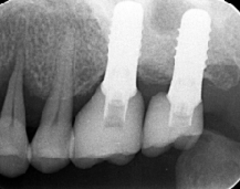

歯周病が進行し、グラグラして物が嚙めず、抜歯してインプラントにしていくことに。

インプラントはストローマンを使用、上部構造はジルコニアセラミックス

費用は2本で総額40万円(税込44万円)(他院の相場だと税込88万円位です)